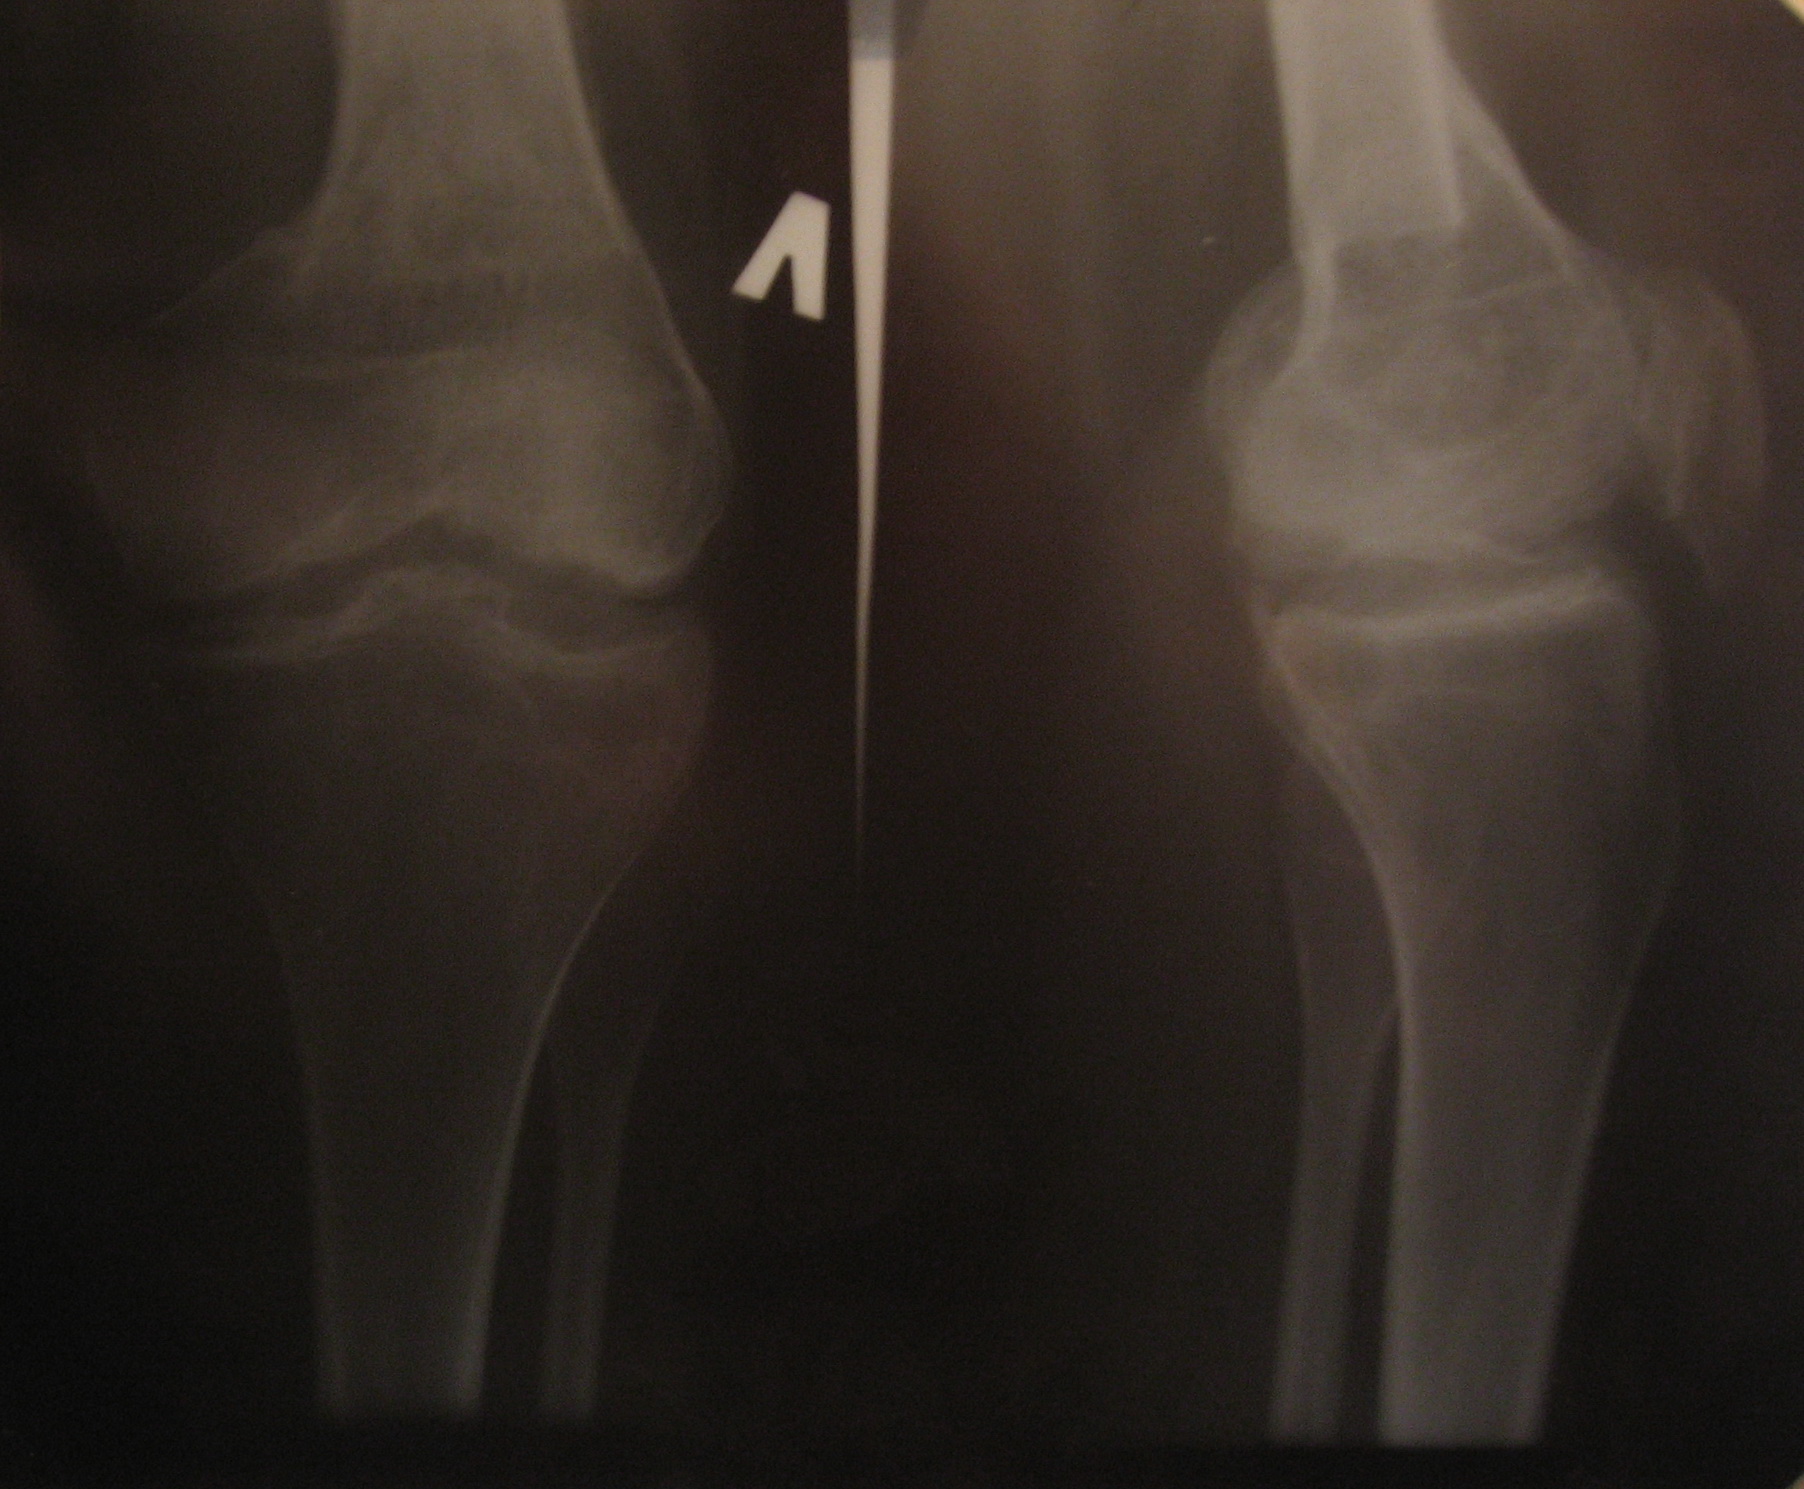

На снимке колену 4 месяца......сейчас 1 год прощел )) щель разрослась, могу сгибать на 45-50 градусов

Ситуация вряд ли может быть адекватно оценена по скудному непрофессиональному описанию. На снимке ничего тревожного не видно, можно движения разрабатывать. Препятствия разработке, скорее всего, обусловлены рубцовым процессом в мышцах. Возможно, и тем заболеванием, которое имелось.